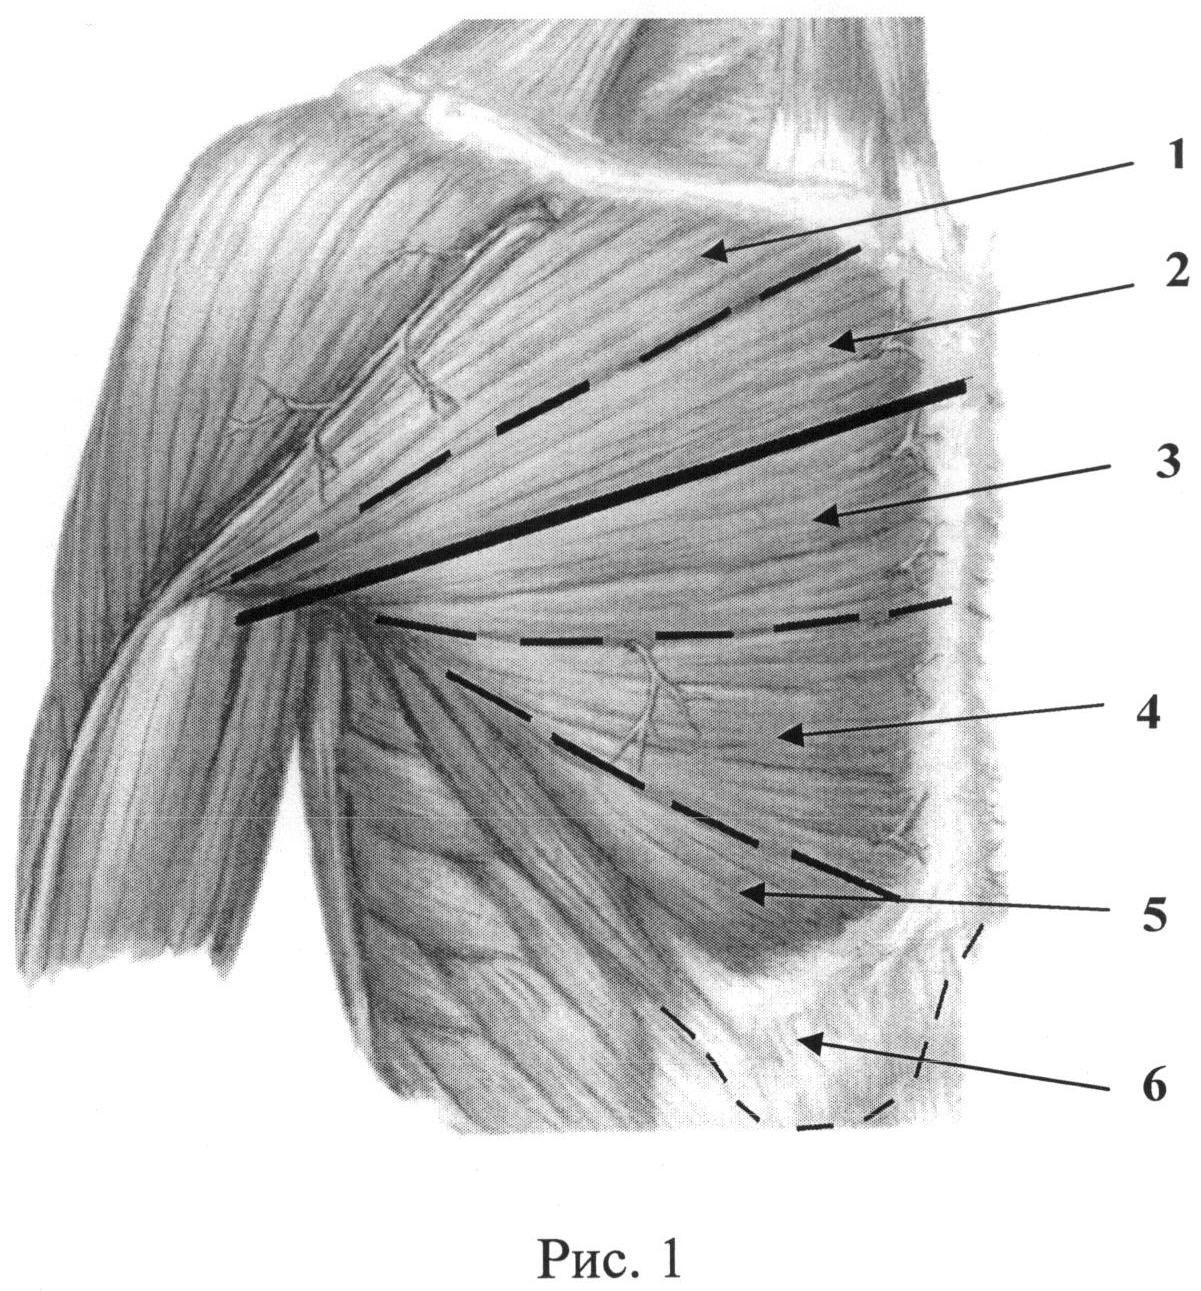

Фотографии поддельтовидной мышцы плечевого сустава